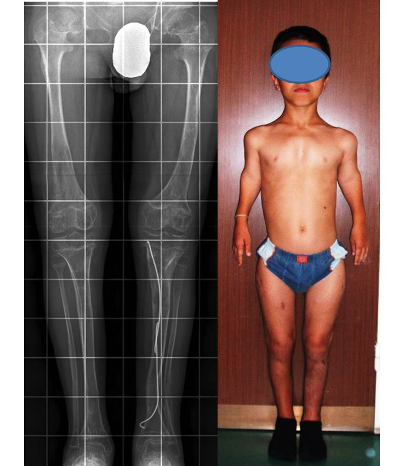

Slede primeri takve rekonstrukcije ekstremiteta (iz arhive prof. D. Popkova i Atlas klinike).

*Rentgenski snimak donjih ekstremiteta i fotografija pacijenta sa ahondroplazijom u procesu lečenja.

*Među etapni rezultat: Produženi donji ekstremiteti, ali predstoji još produžavanje nadlaktica.